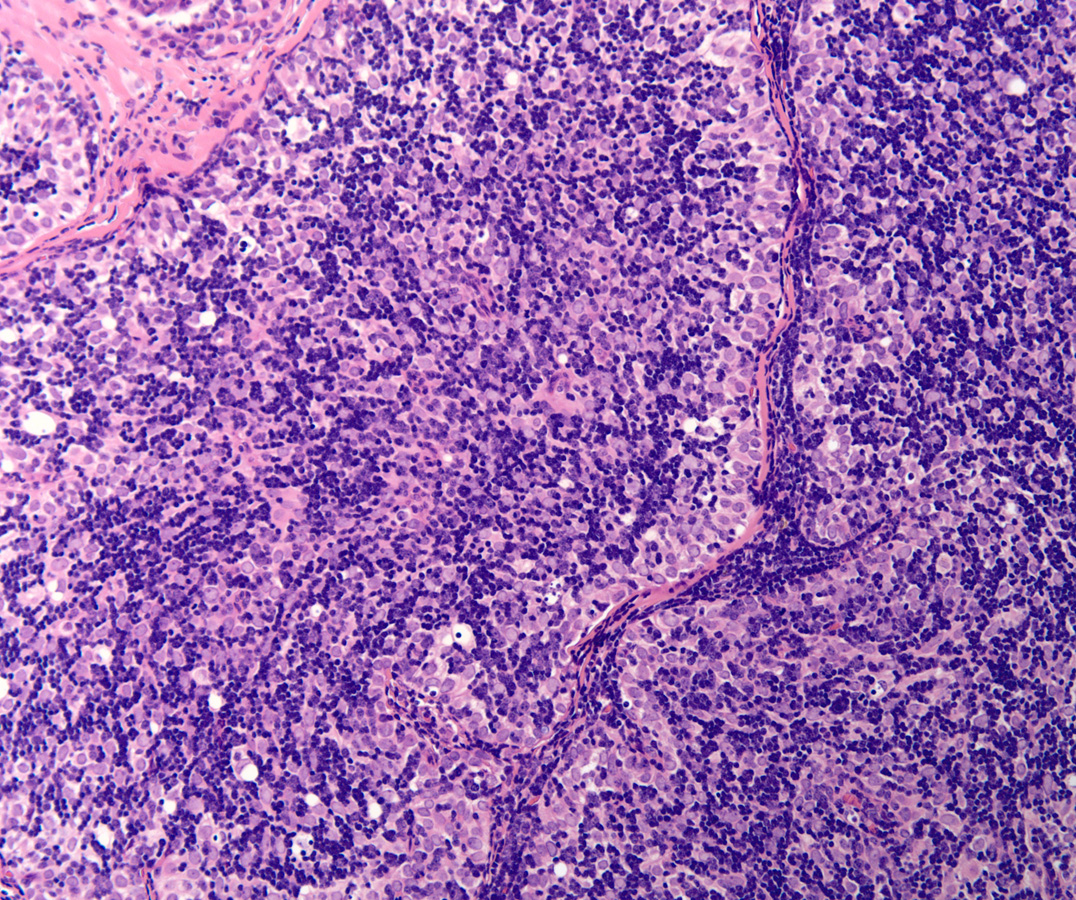

Low power H&E show tumor in below the mesothelial lining. Distinct lobular / organoid appearance noted with two types of cells, small lymphoid cells and large neoplastic cells with clear cytoplasm (bi-phasic pattern). IHC stains showed large cells are cytokeratin positive and small lymphoid cells expressed CD3, CD5 and ntDt (immature thymocytes).

Additional history later revealed a large anterior mediastinal mass with tracheal compression and seeding of pleura. Main tumor was not resectable. Histology (epithelial elements and thymic lymphoid stroma) and IHC stains support an aggressive thymoma, WHO B2, metastatic to pleura. Normal thymic milieu i.e. immature thymocytes often present in metastasis along with neoplastic epithelial component. Metastatic thymoma must be considered in the differential diagnosis with bi -phasic patten as illustrated above.